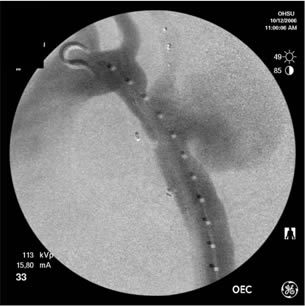

Because of the patient’s prior coarctation repairs and the morphology of the pseudoaneurysm, an endovascular repair was felt to be desirable. Based on preoperative measurements of the CT angiogram, a tapered endoprosthesis 9.5cm in length with 16mm proximal diameter and 20mm distal diameter (W.L. Gore & Associates, Inc.), originally marketed as an iliac limb, was selected for use. The patient was taken to the operating room. After induction of general anesthesia, percutaneous right femoral artery access was obtained and a measuring pigtail catheter was advanced into the distal aortic arch. An aortogram was performed which demonstrated the aortic arch and pseudoaneurysm morphology (Figure 3).